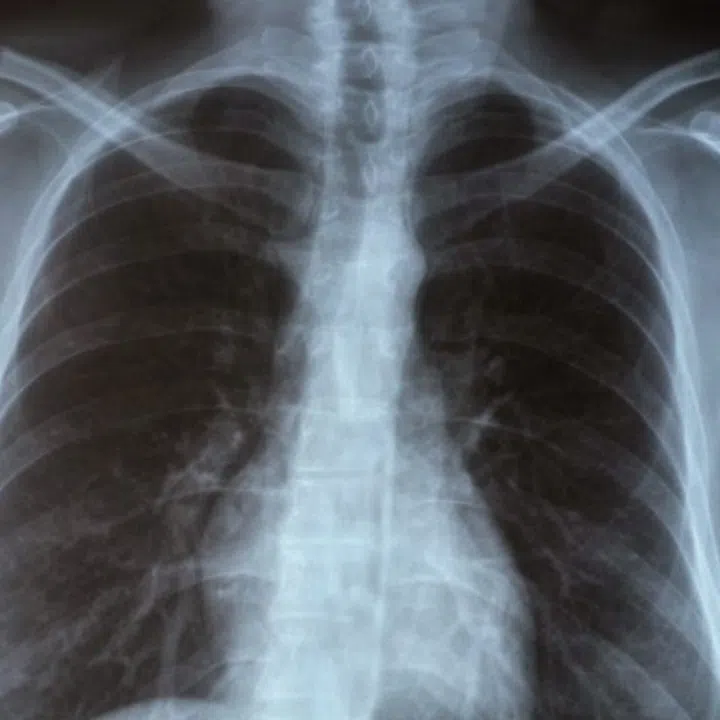

Lung cancer risk factors

Credit: 123rf

Smoking is the strongest risk factor for lung cancer. The risk of lung cancer increases with the number of cigarettes smoked per day and the number of years of smoking. However, quitting smoking can reduce the risk for lung cancer regardless of how many years a person has smoked. The risk of cancer goes down after quitting

Exposure to secondhand smoke, radiation, and asbestos are other risk factors for lung cancer